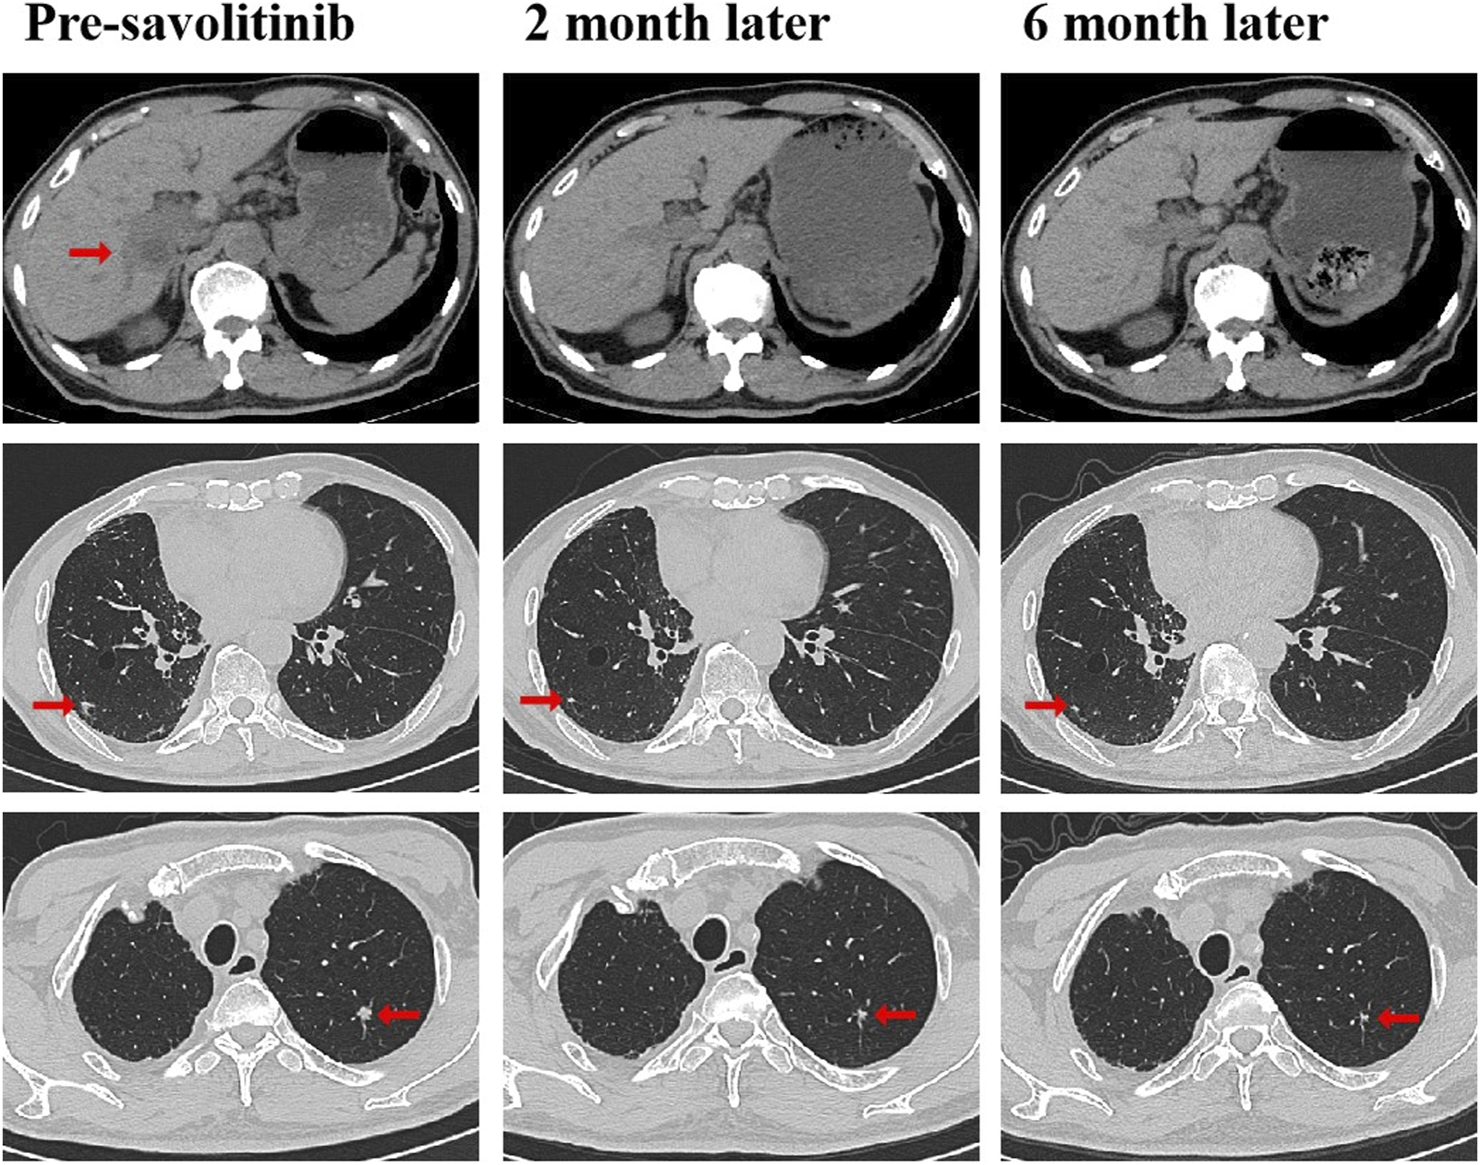

FIGURE 2

CT scans before and after savolitinib treatment. CT scans at pre-savolitinib showed the presence of liver metastasis and bilateral lung metastases. CT scans after treatment with savolitinib showed partial response in bilateral lung lesions and complete response in liver metastasis. CT, computed tomography.

A 79-year-old non-smoking man visited the hospital because of a 5-month history of cough with sputum. The patient was previously in good health, without hypertension and diabetes. A computed tomography (CT) scan revealed a nodule in the right upper lung (the diameter is approximately 1.2 cm), without bone, liver, kidney, or brain metastases. On 9 January 2018, the patient underwent right upper lobectomy plus systematic lymph node dissection and was diagnosed with right upper lung adenocarcinoma (stage IA, pT1N0M0) as the immunohistochemical (IHC) staining indicated the tumor was positive for Napsin A and thyroid transcription factor-1 (TTF-1) (Figure 1). The gene testing of the patient’s pathological tissue revealed the presence of epidermal growth factor receptor (EGFR) exon 21 L858R point mutation. The patient did not receive postoperative adjuvant therapy and underwent regular follow-up. In November 2019, a chest CT scan revealed local recurrence of the residual right upper lobe of the lung. Subsequently, the patient initiated gefitinib treatment at a daily dose of 250 mg. Four months later, the patient stopped taking gefitinib due to progressive lesion growth and then the patient received chest radiotherapy, followed by continuous treatment with a combination of Icotinib and Bevacizumab in November 2020. Due to a significant decline in renal function (serum creatinine level:123umol/L; estimated glomerular filtration rate (eGFR):48.1 mL/min), Icotinib and Bevacizumab were discontinued in November 2022, and the patient was subsequently switched to Osimertinib. In April 2023, the patient’s chest CT revealed interstitial changes in the lungs, which led to the consideration of possible intolerance to Osimertinib, and the treatment was adjusted to Almonertinib. In June 2023, a CT scan showed bilateral lung metastases and a growth of the tumor in the lower segment of the right posterior lobe of the liver, indicating disease progression (Figure 2), then the peripheral blood next-generation sequencing (NGS) testing was conducted, and the NGS testing revealed a novel METex14 skipping mutation (c.2888–23_2888-8delTCTTTCTTTCTCTCTG IVS13, 1.0%), accompanied by a TP53 mutation (p.Y163C, 0.1%) (Figure 3). Combination therapy with Almonertinib and savolitinib were recommended, but the patient chose to receive savolitinib alone at a daily dose of 400 mg after considering the cost. Fortunately, after a 2-month period of treatment, the patient had a partial response in lung lesions and complete response in liver metastasis (Figure 2). As of the time of writing this manuscript, the patient is still taking savolitinib with a progression-free survival (PFS) over 8 months and no significant adverse events have been observed so far. The patient’s treatment process is shown in Figure 4.